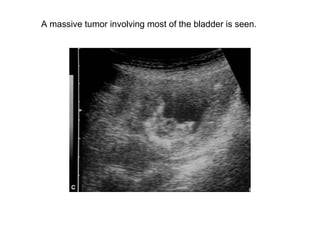

Bladder tumor

A small polypoidal tumor with a narrow base is shown.

A massive tumor involving most of the bladder is seen.